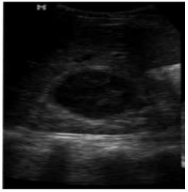

Uma mulher de 17 anos, gestação de 20 semanas, com febre (37,8ºC) foi encaminhada para realização de exame de ultrassonografia renal. O EAS mostrava piúria (20 a 30/campo). A paciente já se encontrava em tratamento com cefalexina, 500 mg VO, três vezes ao dia, que foi mantido por 14 dias. Segue USG realizada:

Corte longitudinal ecográfico do rim direito, mostrando

uma lesão hipecoica bem definida, medindo 48,0mm

Fonte: Vol. 10 • 14ª Edição • março DE 2011 | rbus 21